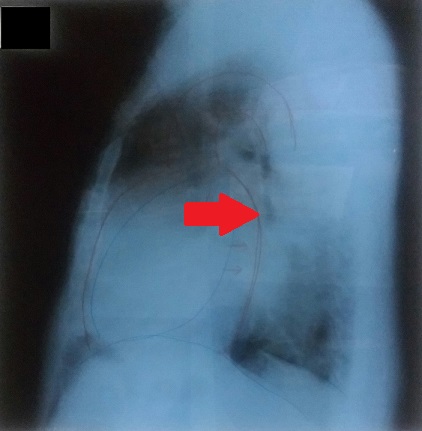

<胸部エックス線>

側面像:心拡大 左心房の拡大も顕著です。

肺水腫の所見の検索

①心陰影の拡大(心・胸郭比↑)CTR=75.8%(基準:50%未満)

以上を認めましたが、胸水貯留をはじめKerley’s B line,vanishing tumorなどの所見は認めませんでした。